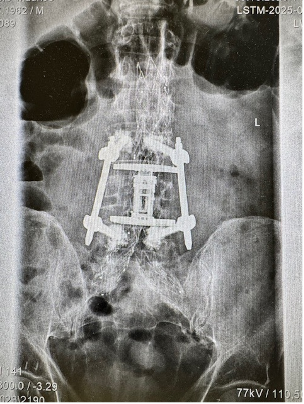

In more complex fractures, stabilization of the spine using screws and rods may be required.

These procedures help restore spinal alignment and provide long-term stability.

Whenever possible, these procedures are performed using minimally invasive techniques, which allow smaller incisions, less tissue disruption, and faster recovery.

Patient fell from ladder and developed lumbar L4 fracture, he was addressed in minimal invasive technique with L4 replacement and stabilisation. He was able to ambulate without any aids on day 1 after surgery